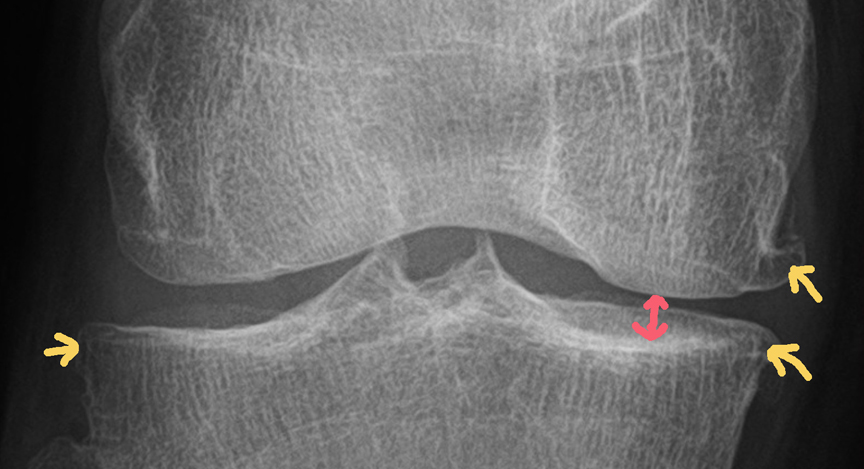

Das obere Röntgenbild zeigt das linke und das untere Bild das rechte Knie.

Die roten Markierungen zeigen den jeweils deutlich verengten Gelenkspalt an den Knieinnenseiten und die orangen Pfeile zeigen die sogenannten Osteophyten.

Osteophyten sind Knochenanbauten, die sich bei fortgeschrittenen Arthrosen bilden.

Was man auf den Röntgenbildern außerdem nicht sehen kann, sind die weiteren Schäden an den Kien wie: Knorpelschäden bis Grad 4, Knochenmarködeme, Meniskusschäden, Bakerzyste, Wasseransammlungen etc., die natürlich auch noch teils heftig vorhanden sind und für mein unrundes und verkorkstes Gangbild sorgen.